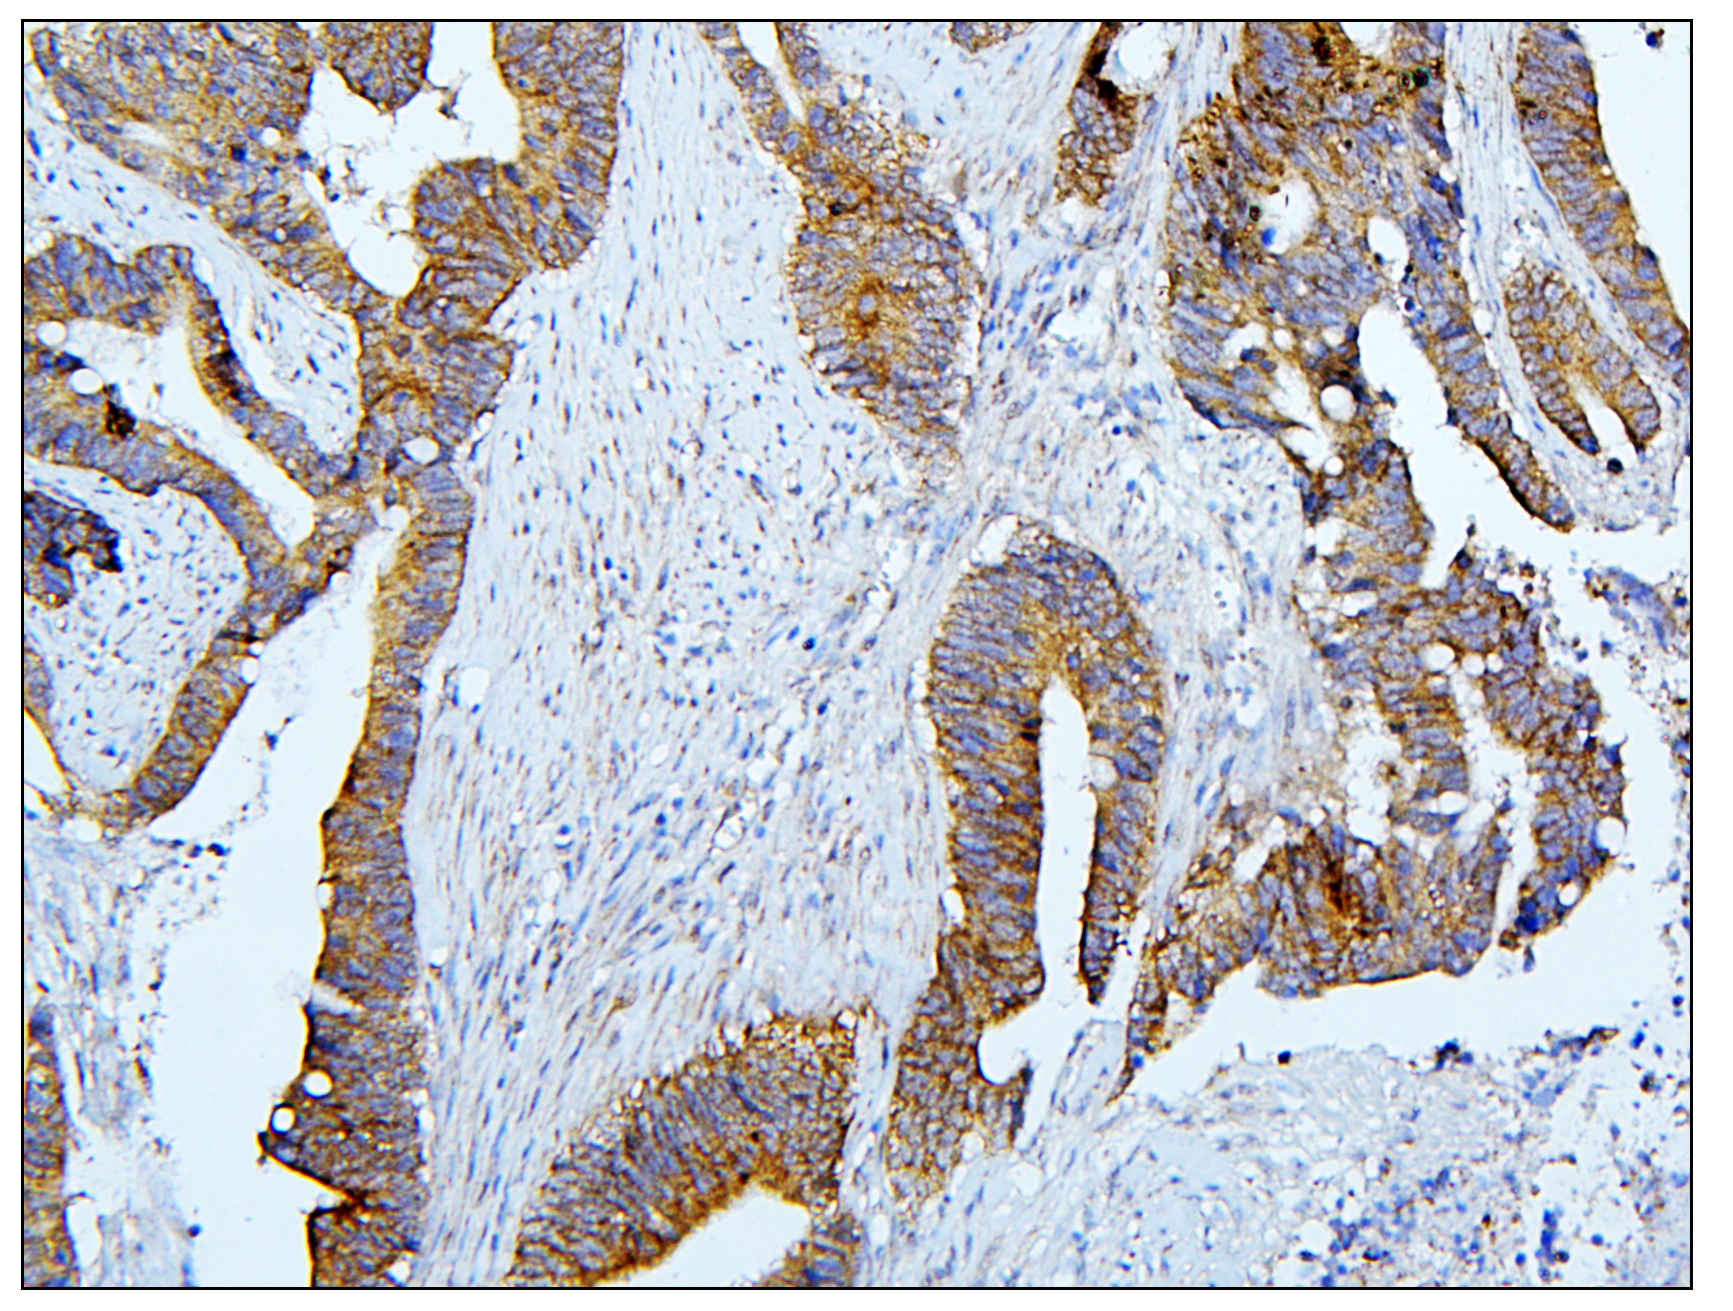

IHC analysis of BubR1/BUB1B using anti-BubR1/BUB1B antibody (A01564-1).

BubR1/BUB1B was detected in a paraffin-embedded section of human colon cancer tissue. Biotinylated goat anti-rabbit IgG was used as secondary antibody. The tissue section was incubated with rabbit anti-BubR1/BUB1B Antibody (A01564-1) at a dilution of 1:200 and developed using Strepavidin-Biotin-Complex (SABC) (Catalog # SA1022) with DAB (Catalog # AR1027) as the chromogen.